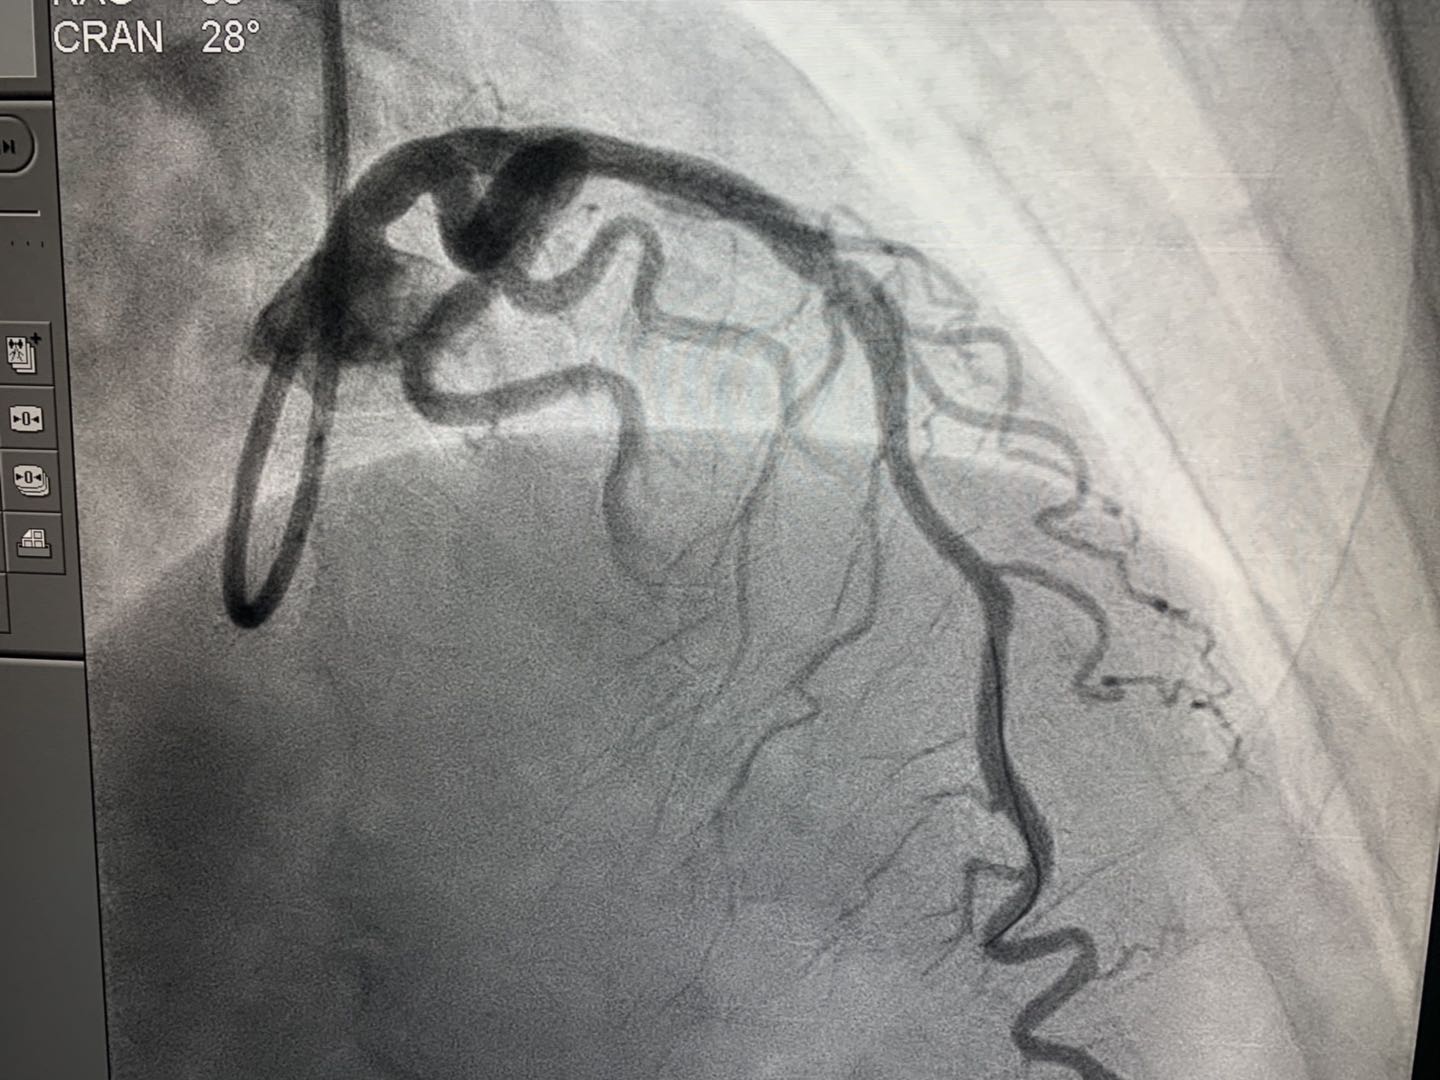

2019年4月16日,新疆首例生物可吸收心脏支架植入术在Beat365中国唯一官方网站附属中医医院(自治区中医医院)成功实施。医院心脏中心冠脉介入团队在武刚主任带领下,为一例50岁男性患者冠状动脉前降支近端成功植入NeoVas生物可吸收支架一枚。术中、术后采用光学相干断层扫描(OCT)对冠脉病变及植入支架进行评估。手术顺利,患者体征平稳。

NeoVas支架,全称为“生物可吸收冠状动脉雷帕霉素洗脱支架系统”,其基体及药物载药涂层分别由可吸收材料制成,支架基体和涂层在体内逐步生物降解和吸收,无永久性支架存患者体内。简单讲,传统支架是金属制成的,一旦进入人体将永久存在,此次使用的可吸收支架是由可降解材料制成,进入人体后会逐渐溶解并消失,不会在体内留下异物,避免了患者受到血管二次堵塞风险。

心内二科武刚主任介绍,心脏支架是心脏介入手术中最常用的医疗器械,具有疏通动脉血管的作用。由于这个“外来物”一旦进入人体后就要终身携带,这也让一些患者特别是年轻的心脏病人产生担忧。冠心病介入治疗(PCI)已经经历了三代技术发展:单纯球囊扩张术、金属裸支架(BMS)和药物洗脱支架(DES)。生物可吸收支架是冠脉支架的发展方向,可解决药物洗脱金属支架永久异物的痛点。目前世界范围内应用的支架大部分是第三代支架——药物洗脱支架,由于其材质为金属的,植入后会在人体内永久存留金属异物。

武刚主任医疗团队此次植入可吸收支架的材料为聚乳酸等,在植入体内后2-3年可完全降解,而且可以恢复血管的功能和弹性,不会永久存留,所以被认为是冠心病治疗的第四次革命。同时对于金属支架过敏的冠心病患者是个很好的选择。预计未来可吸收支架会被广泛使用,冠心病介入治疗将进入新的时代。(介入治疗室魏玲)